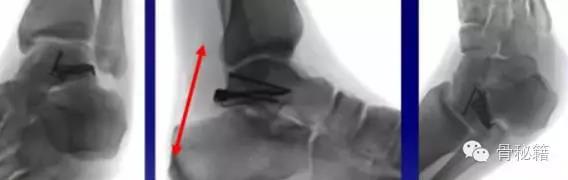

对于颈部的骨折,如果一侧钢板的位置不佳,则容易造成另外一侧的骨折裂开所以最好的固定是一侧用钢板固定,另外一侧可采用螺钉进行加压,避免另外一侧开口

要点!!1、骨折严重合并脱位的一定要早期临时外架牵引复位和维持一定要早期临时外架牵引复位和维持一定要早期临时外架牵引复位和维持重要的说三遍2、尽量保护血运,用单侧入路3、尽量避免关节面内置物4、注意皮肤软组织情况